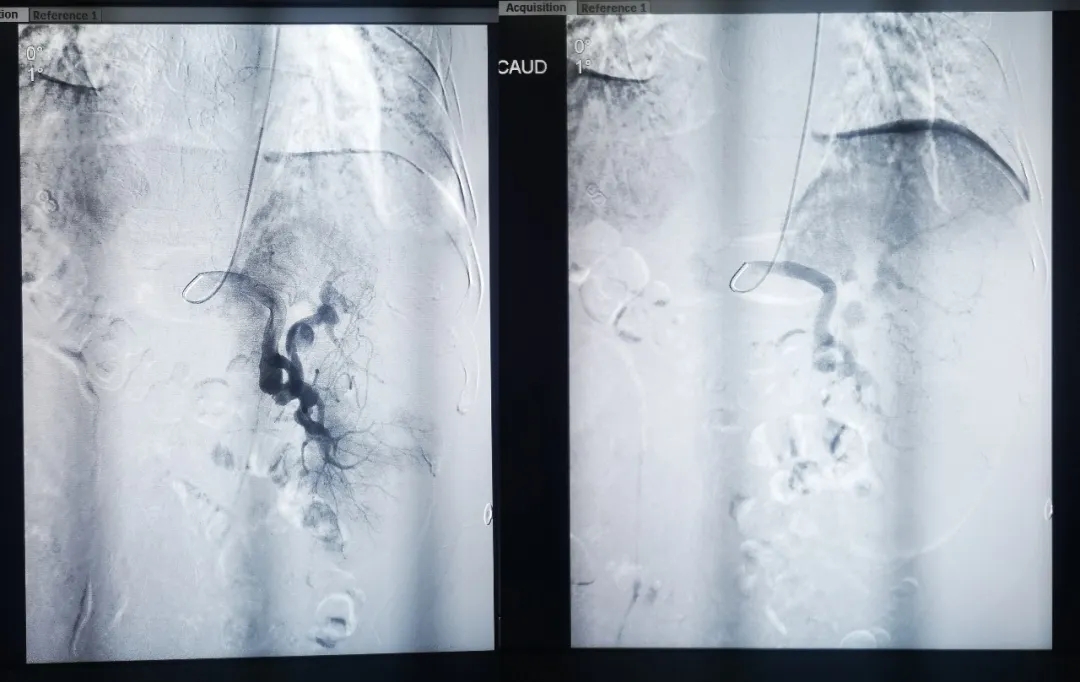

74岁的孙大爷是一名肝肿瘤患者,经过综合评估后,认为肝动脉栓塞术是治疗首选方案。传统方法需要在大腿根部的股动脉穿刺建立治疗通路,手术后需压迫大腿根部穿刺点,且24小时内不能下床活动。孙大爷平时腰痛,无法耐受术后的漫长卧床过程。我院介入血管外科王立军主任决定通过手腕部的桡动脉穿刺,实施介入治疗。6月26日,介入血管外科团队为其进行经手腕部桡动脉穿刺肝动脉栓塞术,术后一小时,孙大爷就可以下床活动了,术后三天就出院了。 64岁的刘大爷患有脾功能亢进,需要进行脾动脉栓塞手术,由于刘大爷长期贫血,体质较差,传统介入治疗术后长期卧床无疑给刘大爷增加更多痛苦。王立军主任决定为其进行经手腕部桡动脉穿刺脾动脉栓塞术,术后3天,患者康复出院。 此项技术的成功开展,为广大肿瘤、出血患者开辟了新的治疗途径。 经桡动脉穿刺进行介入治疗的优点 1.术后无需腿部制动,无需24小时卧床,做完手术后即刻行动自如; 2.提高了就医质量和感受; 3.缩短了住院时间,节省了经济费用; 4.减少了术后并发症。